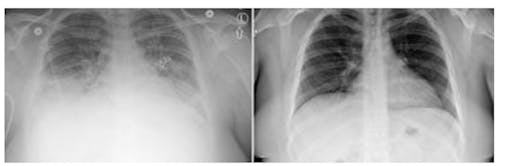

Sickened lungs show up as cloudy on the left X-ray, and clear after treatment of one suspected VAPI patient in Utah. (Courtesy University of Utah)